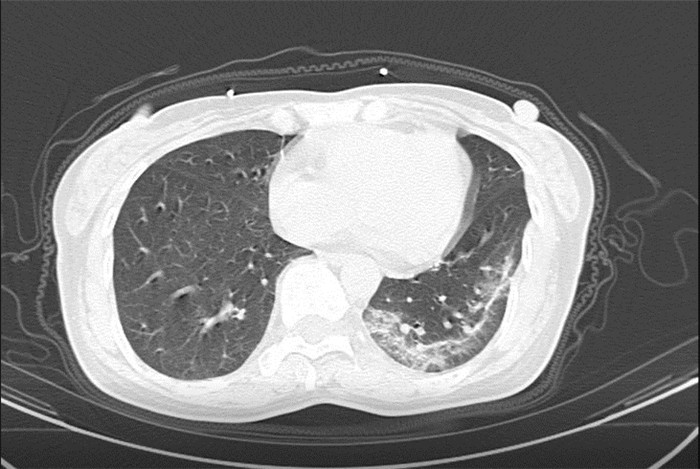

武漢大學(xué)中南醫(yī)院影像科副主任張笑春教授發(fā)現(xiàn),目前武漢市家庭聚集性發(fā)病較多,而且大多起病隱匿,一次甚至多次核酸陰性,無任何臨床癥狀,CT檢查卻已顯示為病毒性肺炎特征。

為了盡快篩查新型冠狀病毒肺炎患者,醫(yī)院會選擇影像診斷作為早期發(fā)現(xiàn)新型冠狀病毒感染的肺炎的重要一環(huán)。

CT為當(dāng)前首選篩查與診斷的主要影像學(xué)手段,胸部CT的病毒性肺炎檢出率高。

方舟CT(CT Ark)可以滿足全面的臨床功能,配置16層、32層、64層、128層CT,實(shí)現(xiàn)了低劑量掃描要求,配合NDI微劑量迭代技術(shù),智能毫安調(diào)控技術(shù),使各種場合下、各部位低劑量掃描得以實(shí)現(xiàn);超高分辨率CT病灶靶掃描,使病灶的密度顯示更加精確,能夠顯示病灶內(nèi)輕度的密度變化,有利于小病灶的密度定量分析和及時診斷。